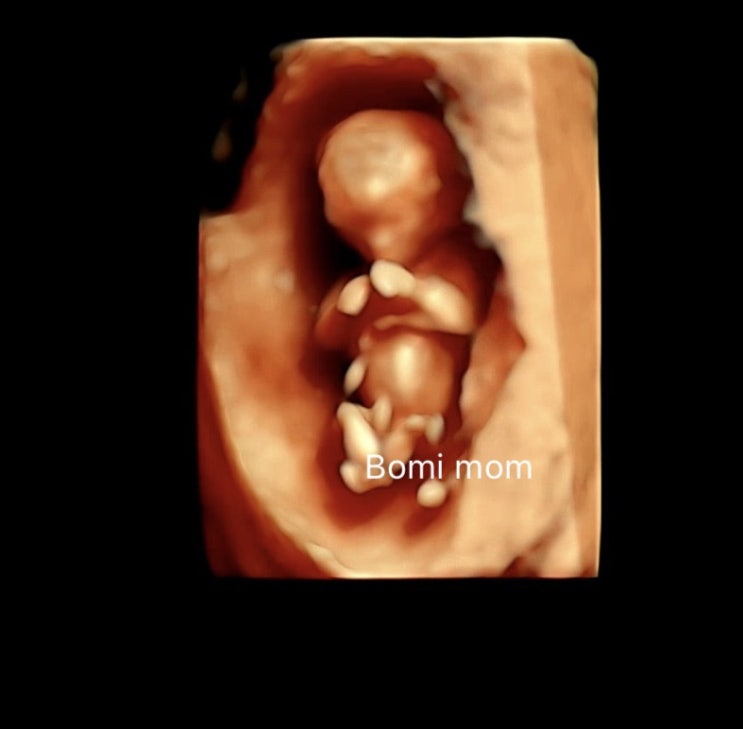

17주 아기성별 | 2차기형아검사

#2차기형아검사 #17주성별 #2차기형아검사비용 1차 기형아 검사 때 정밀초음파로 찍었던 사진? 지금은 1...